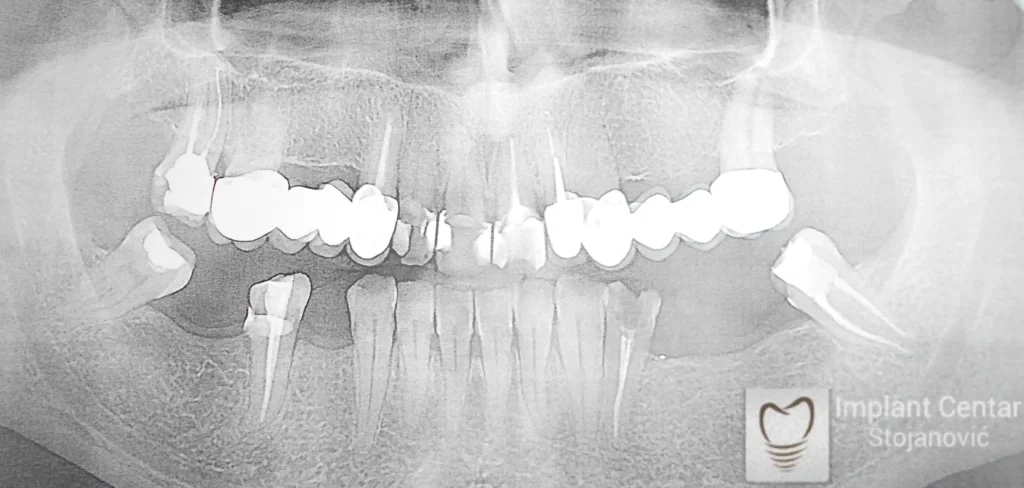

Na slici 1. i slici 2. prikazan je izgled pacijenta pre početka terapije – klinički i rendgenološki.

Nakon vađenja zuba, ugrađeni su implantati. Na slici 3 prikazan je ortopan snimak sa ugrđenim implantatima. Tokom perioda osteointegracije, pacijent je bio zbrinut fiksnim privremenim krunicama na implantatima, koje su izrađene samo dva dana nakon hirurške intervencije.